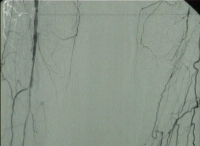

DSA preoperatoria del paciente:

PM 311-3

Abb. 3: A. poplitea Abschnitt PI rechts füllt sich wieder

PM 311-4

Abb. 4: Teilverschlüsse der Unterschenkelarterien bds., Verschluss der A. poplitea Abschnitt PIII links